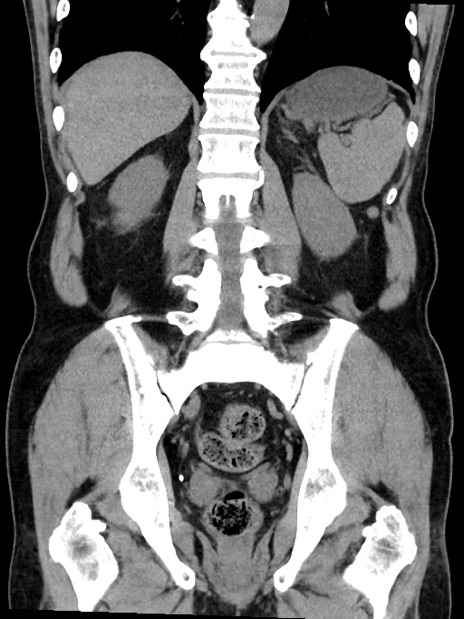

症例35(冠状断像)

【症例】70歳代 男性

【主訴】腹部膨満、嘔吐

【現病歴】昨日より腹部膨満感出現。本日増悪し、仙痛出現。嘔吐あり、受診。

【既往歴】糖尿病、胆摘後

【身体所見】BP 149/80mmHg、HR 74/min、BT 35.9℃、腹部:膨満、軟、圧痛なし。腸雑音減弱あり。上腹部正中切開瘢痕あり。

【データ】WBC 13500、CRP 1.72